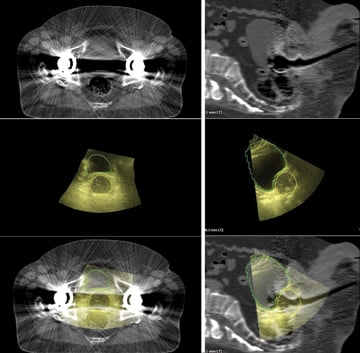

Axial (left column) and sagittal (right column) images of a patient with bilateral hip prostheses. Top images (Figure 1) are 3-D CT, middle (Figure 2) are Clarity 3-D ultrasound images with the prostate and bladder contoured, and bottom images are the fused 3-D datasets.

At the University of Vermont/Fletcher Allen Health Care, we have adopted the routine use of transabdominal ultrasound/CT image fusion in the treatment planning process. This approach has been particularly helpful in patients who present challenges to standard imaging, including those with metal prosthetic hip arthroplasties (Figure 1). In our ongoing comparison trial of Clarity Autoscan with TPUS compared to MRI for image fusion, early experience suggests that a TPUS obtained in the simulation position and acquired simultaneously with the planning CT is superior to an MRI obtained on a different machine, at a different time with different amounts of bladder and rectal filling.